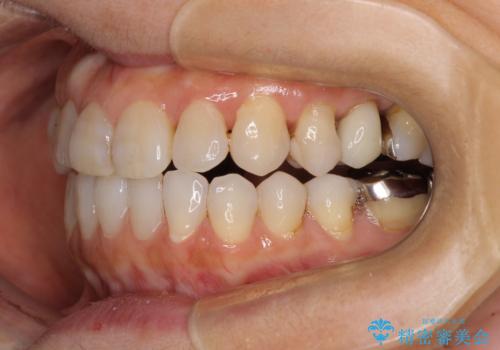

前歯の突出感と上下の隙間 インビザラインによる矯正治療

- 前歯の上下スペースと前歯の隙間を気にして来院された患者様です。

インビザラインにより上下の前歯の隙間を閉じながら、IPRを用いて口元の突出感を合わせて改善していくこととしました。

上下の隙間に舌が入り込むことが、すきっ歯やオープンバイトの原因であったため、舌の筋肉のトレーニングも並行して行い、後戻りの抑制を図りました。